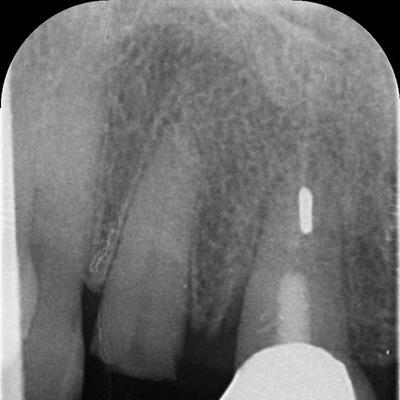

• Dental X-Ray Photo

• Digital X-Rays (faster results)